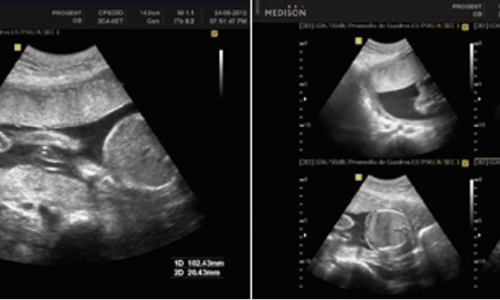

ECOGRAFIA que se realiza después de la semana 28 de gestación y en adelante. Es un estudio realizado mediante ultrasonografía que evalúa los movimientos fetales (MF), tono fetal (TF), movimientos respiratorios (MR), Índice de líquido amniótico (ILA) y la monitoria fetal para la evaluación del bienestar del bebé. Se realiza para determinar el bienestar del feto, el especialista llegará a la conclusión de si hay un correcto bienestar fetal, o si hay algún riesgo de hipoxia y acidosis.